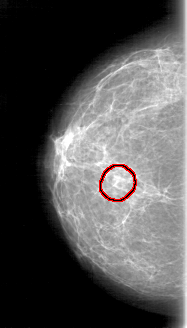

FILE: D_4071_1.RIGHT_MLO.OVERLAY

TOTAL_ABNORMALITIES 1

ABNORMALITY 1

LESION_TYPE MASS SHAPE LOBULATED MARGINS OBSCURED

ASSESSMENT 0

SUBTLETY 2

PATHOLOGY BENIGN

TOTAL_OUTLINES 1

BOUNDARY